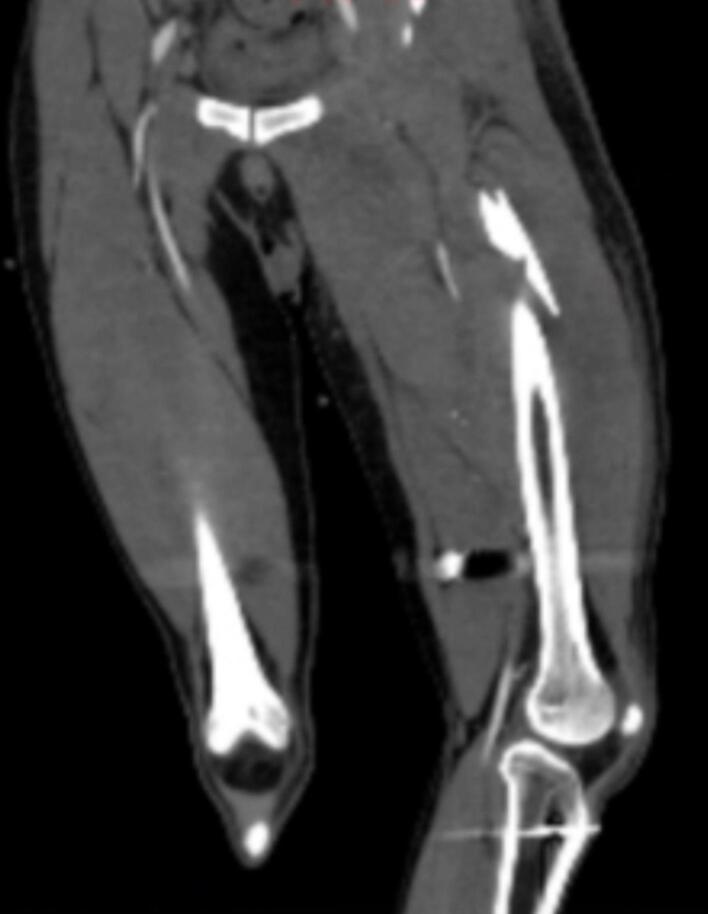

A 27-year-old male presented to the emergency department with a gunshot to the right buttock. Initial assessments revealed a left femoral shaft fracture, the right buttock as the bullet inlet and the medial portion of the left thigh as an outlet, with no other significant findings. He underwent external fixation for the left femoral fracture. On the seventh day of admission, the patient experienced two episodes of massive melena and hypovolemic shock. The patient underwent an upper endoscopy without any remarkable findings. Also, we performed an emergent laparotomy to find the source of upper gastrointestinal bleeding (GIB); however, no evidence of upper GIB was found. Then, the patient underwent CT angiography, which subsequently identified a deep femoral artery pseudoaneurysm. Also, we performed a colonoscopy to investigate the source of GIB, revealing an orifice on the rectal wall. The patient underwent open surgery for a pseudoaneurysm. During surgery, a tract from the pseudoaneurysm of the deep femoral artery to the rectum was discovered, leading to the ligation of the deep femoral artery branch. After recovery from the operation and completion of the orthopedic treatment, the patient was discharged in an appropriate condition.

一名27岁男性因右臀部枪伤被送往急诊科。初步评估显示左股骨干骨折,右臀部为子弹入口,左大腿内侧为出口,无其他显著发现。他接受了左股骨骨折的外固定治疗。入院第7天,患者出现两次大量黑便和低血容量性休克。患者接受了上消化道内镜检查,未发现任何异常。此外,我们进行了急诊剖腹探查以寻找上消化道出血(GIB)的来源;然而,未发现上消化道出血的证据。然后,患者接受了CT血管造影,随后发现了股深动脉假性动脉瘤。我们还进行了结肠镜检查以调查GIB的来源,发现直肠壁上有一个开口。患者接受了假性动脉瘤的开放手术。手术中,发现了一条从股深动脉假性动脉瘤通向直肠的通道,导致股深动脉分支结扎。术后康复并完成骨科治疗后,患者病情好转出院。